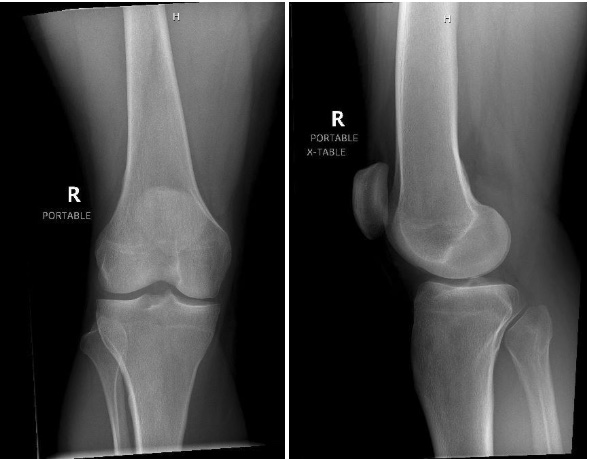

The osteopathic manipulative technique of muscle energy, employing reciprocal inhibition, involved carefully positioning the hamstring just short of causing discomfort. The patient was then instructed to engage their quadriceps by extending their leg toward the provider and performing an isometric contraction. Subsequently, as the patient exhaled and relaxed, the hamstring was gently stretched to a new limit. This procedure was repeated five more times until full extension was successfully achieved.

Following this, the patient’s knee was securely immobilized using a knee brace, and a new XR was obtained. New XR obtained post treatment as seen in Figure 2.